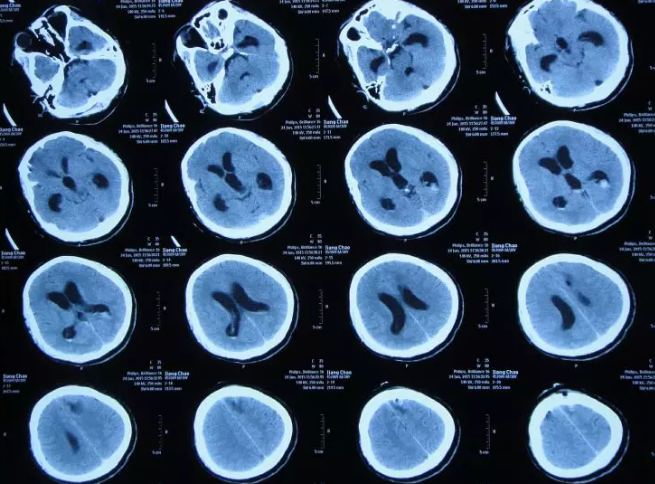

第三脑室扩大ct图

影像医学显示患者脑室增大

呈球样扩张的三脑室提示梗阻性脑积水明显

冠状位显示三脑室扩张,脑积水明显

经第三脑室断层

三脑室层面 三脑室上层面

50mm三脑室后部层面 1-侧脑室前角 2-第三脑室后部 3-侧脑室三角区 4

第三脑室上部层面

正常颅脑ct表现:三脑室下部层面 表现